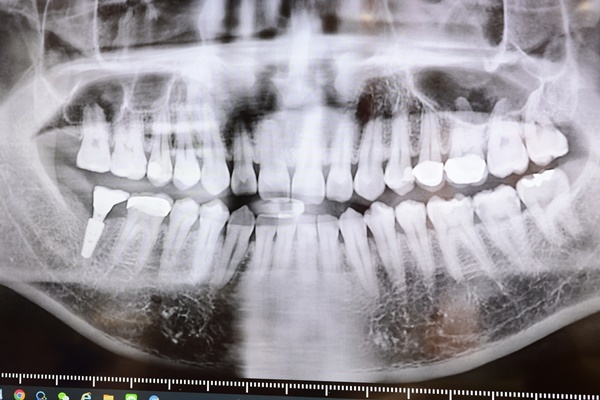

進行植牙諮詢前會有專人引導做X光片拍攝

第一次見識到有如太空艙般想啟航飛行的感覺

拍攝片子前護理師會將一件厚重鉛衣讓病患穿上

用意是要杜絕輻射量對身體造成影響

所以拍攝前護理人員都會詢問有沒有懷孕或是身體不適的問題